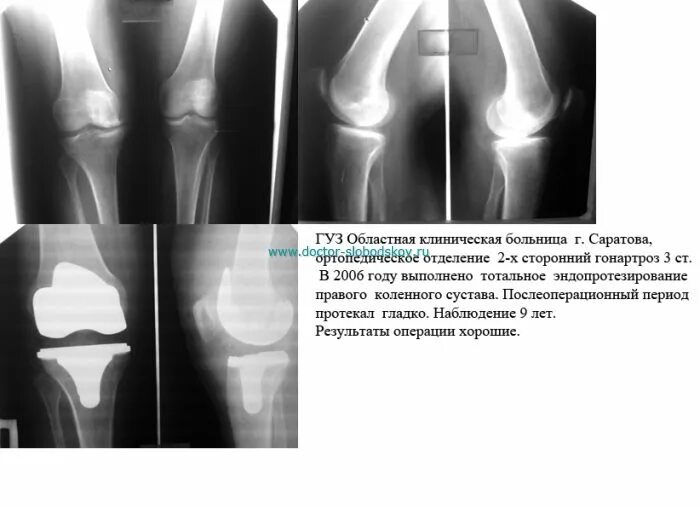

Квота на операцию коленного сустава как получить